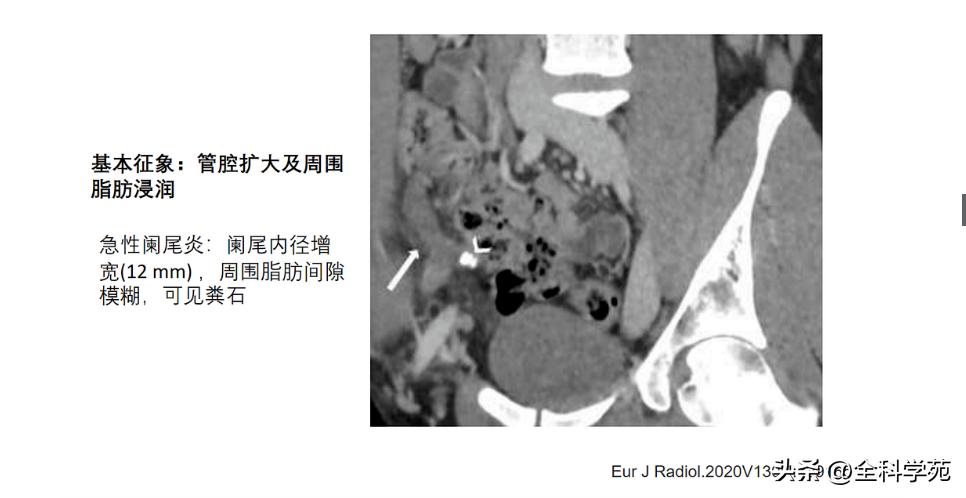

◆ 阑尾的内径增宽

> 10 mm

6-10 mm 伴阑尾壁增厚、壁明显强化,周围脂肪间隙模糊或分层(靶征或牛眼征,表明粘膜下水肿的液体含量vs 气体含量

◆ 阑尾周围脂肪密度增高/模糊与腹腔其他部位的脂肪比较,CT表现为脂肪密度增高,T2压脂为高信号